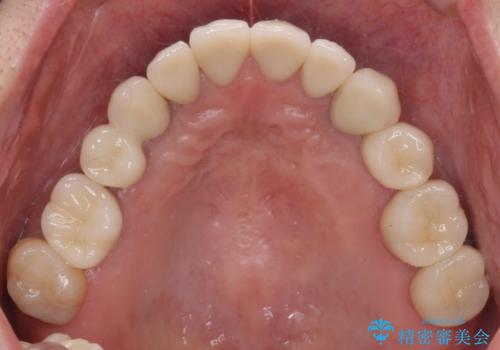

安定する噛み合わせの位置を探りながらの治療となりました。

最終的に非常に安定した咬合関係を構築できたので、しっかりとどんな食事でも楽しめると同時に、清掃性も高く清潔な口腔内環境を確立できました。